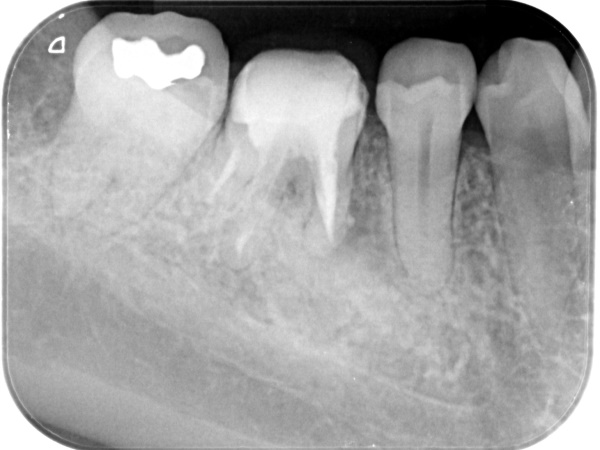

根管治療終了後3か月経過